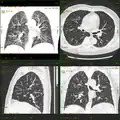

Iterative Korrektur in der Computertomografie: 1 mm Schichtdicke, 120 kV, 20 mAs. Links gefilterte Rückprojektion, Mitte iterative Korrektur erste Generation, rechts iterative Korrektur modellbasiert. Insbesondere bei wenig Dosis und dünnen Schichten ist die deutliche Reduktion des Rauschens im Bild gut zu erkennen. Hier apikaler Pneumothorax rechts.

Vom CT aufgenommene Rohdaten werden mit Ausnahme der allerersten Geräte (EMI Mark1) durchgängig mit Hilfe der gefilterten Rückprojektion in Schnittbilder umgerechnet.[24] Da die gefilterte Rückprojektion allerdings nur in flachen 2D-Schichten theoretisch exakt funktioniert, entstehen bei Mehrschicht- und Spiral-CT Systemen Bildartefakte, die mit iterativen Korrekturverfahren abgemildert werden können.[25] Mit Hilfe solcher Verfahren kann auch das Bildrauschen derart verbessert werden, dass die für eine Untersuchung nötige Strahlendosis bei gleichbleibender Bildqualität um 30 bis 60 % gesenkt werden kann. Bei GE wird der Algorithmus ASIR (Adaptive Statistical Iterative Reconstruction) bzw. MBIR (Model based iterative Reconstruction) genannt; ASIR ist seit dem Jahr 2009 in kommerziell erhältlichen Geräten verfügbar, MBIR noch in Entwicklung; Philips nennt seinen Algorithmus iDose bzw. IMR, bei Siemens wird er IRIS (Iterative Reconstruction in Image Space) genannt und bei Toshiba AIDR (Adaptive Iterative Dose Reduction).[26] In ersten Studien konnten durch ASIR Untersuchungen mit im Mittel 2,6 mSv anstatt wie bisher 3,8 mSv durchgeführt werden. Laut Herstellerangaben ist das Potential des Verfahrens bislang (Stand 2010) noch nicht voll ausgenutzt; die Strahlenbelastung kann künftig bei gleichbleibender Bildqualität durch Einsatz von erheblich mehr Rechenleistung nochmals weiter reduziert werden.[27][20]